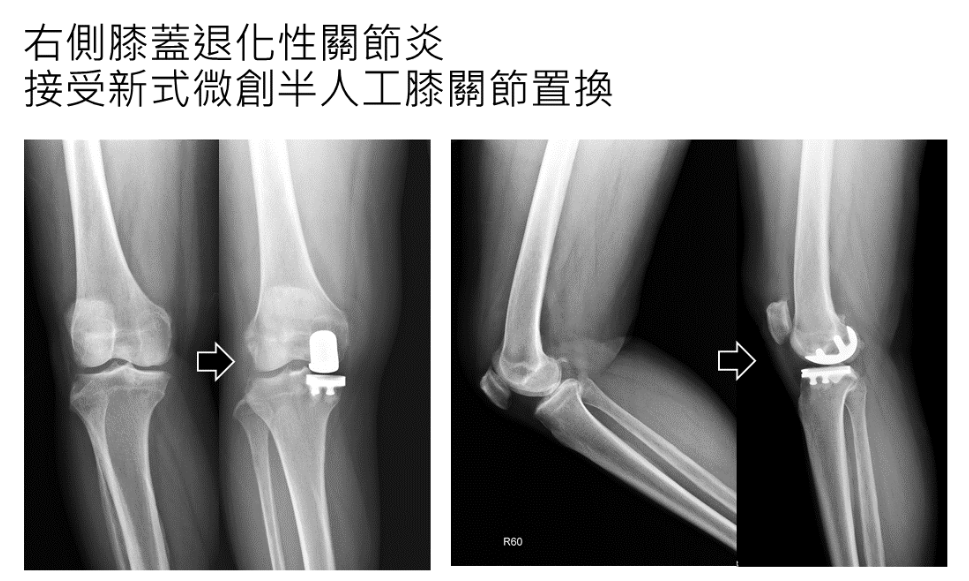

64歲患者的重生案例

一位64歲個案長期受右膝內側疼痛折磨,連走路、爬樓梯都感到困難。經微創關節中心張建鈞醫師詳細評估,其韌帶結構穩定且磨損侷限於內側。

治療方案: 接受新式微創 UKA 手術。

術後表現: 傷口小且出血極少,術後第一天即開始物理治療,兩週後已能自如地穿梭於公園。